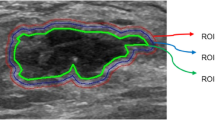

The preoperative abdominal enhanced CT image data of all patients were collected from the ICPACS workstation of the CT room at the Imaging Department of our institution and exported in.DICOM format. For all the image modality, the slices were resampled to 1*1*1cm3, and the intensity range were normalized to a mean value of 0 and standard deviation of 1 (z score standardization). Doctor A, a senior diagnostic imaging doctor, used ITK-Snap software (https://www.itksnap.org) to delineate the (ROI) of the lesion in the third phase of enhanced CT. For 2D delineation, the scope included the layer with the largest lesion surface area, and for 3D delineation, the scope covered all possible areas of the target lesion. During the delineation, necrosis, blood vessels, and other structures were eliminated as completely as possible (Fig. 2). Two weeks later, doctor A randomly selected data of 30 patients to perform ROI delineation again to evaluate the intra-group consistency of ROI delineation (intra-ICC). To evaluate the between-group consistency of ROI delineation (inter-ICC), another radiologist, B, also drew the ROIs on the 30 patients’ images independently.